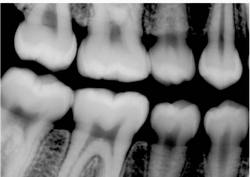

However, the human eye is only capable of distinguishing 32 shades of gray, which corresponds to a spatial frequency ranging from 5 to 7 lp/mm without magnification. The question then becomes, does the magnitude of a digital system spatial resolution above about 10 lp/mm make any diagnostic difference in the clinician’s ability to recognize pathosis radiographically? The answer is still being debated, but at least from our viewpoint, which can be supported from some of our initial investigations into this question, 1,2 probably not. Therefore as an example, can dentists recognize carious lesions confined to enamel as well using digital images as compared to radiographic film? Probably so, but further investigation is needed. An example of an image taken with a Soredex OpTime (spatial resolution of 12.5 lp/mm) is shown in Figure 1. An arrow is pointing to noncavitated proximal carious lesions.

Finally, overall appearance of the image can be a very subjective assessment. Most dentists prefer image appearance and definition to be as much like conventional film as possible. The bitewing image in Figure 2 was taken with a CCD sensor and the bitewing image in Figure 3 was taken with a Soredex OpTime PSP sensor using a dry skull to maximize the definition of bone. Both images were made using the same kV, mA, and time, using the same enhancement features of the particular post-processing software utilized by the imaging system. From a purely subjective viewpoint, some dentists may prefer one image over the other depending on their personal likes and dislikes.